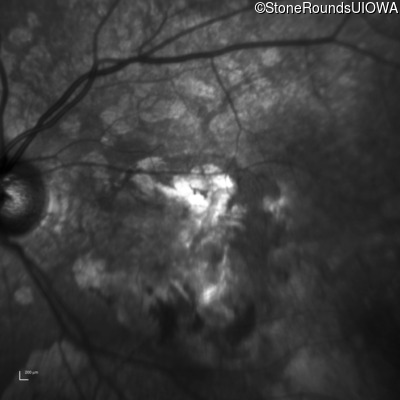

Infrared Fundus Photograph - Right - 20/200 +2

Exemplar